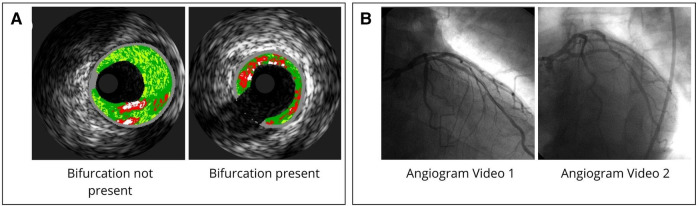

Despite advancements in early detection and treatment, atherosclerosis remains the leading cause of death across all cardiovascular diseases (CVD). Biomechanical analysis of atherosclerotic lesions has the potential to reveal biomechanically instable or rupture-prone regions. Treatment decisions rarely consider the biomechanics of the stenosed lesion due in-part to difficulties in obtaining this information in a clinical setting. Previous 3D FEA approaches have incompletely incorporated the complex curvature of arterial geometry, material heterogeneity, and use of patient-specific data. To address these limitations and clinical need, herein we present a user-friendly fully automated program to reconstruct and simulate the wall mechanics of patient-specific atherosclerotic coronary arteries. The program enables 3D reconstruction from patient-specific data with heterogenous tissue assignment and complex arterial curvature. Eleven arteries with coronary artery disease (CAD) underwent baseline and 6-month follow-up angiographic and virtual histology-intravascular ultrasound (VH-IVUS) imaging. VH-IVUS images were processed to remove background noise, extract VH plaque material data, and luminal and outer contours. Angiography data was used to orient the artery profiles along the 3D centerlines. The resulting surface mesh is then resampled for uniformity and tetrahedralized to generate the volumetric mesh using TetGen. A mesh convergence study revealed edge lengths between 0.04 mm and 0.2 mm produced constituent volumes that were largely unchanged, hence, to save computational resources, a value of 0.2 mm was used throughout. Materials are assigned and finite element analysis (FEA) is then performed to determine stresses and strains across the artery wall. In a representative artery, the highest average effective stress was in calcium elements with 235 kPa while necrotic elements had the lowest average stress, reaching as low as 0.79 kPa. After applying nodal smoothening, the maximum effective stress across 11 arteries remained below 288 kPa, implying biomechanically stable plaques. Indeed, all atherosclerotic plaques remained unruptured at the 6-month longitudinal follow up diagnosis. These results suggest our automated analysis may facilitate assessment of atherosclerotic plaque stability.